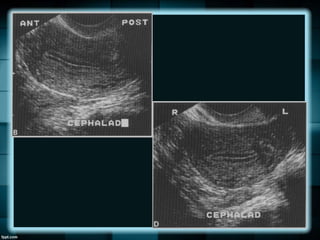

En el útero la flexión se refiere al eje del

cuerpo uterino al eje del cérvix

Mientras que la versión se refiere al eje del

cérvix en relación con la vagina.

En el úterola flexión se refiere al eje del cuerpo uterino al eje del cérvix Mientras que la versión se refiere al eje del cérvix en relación con la vagina.